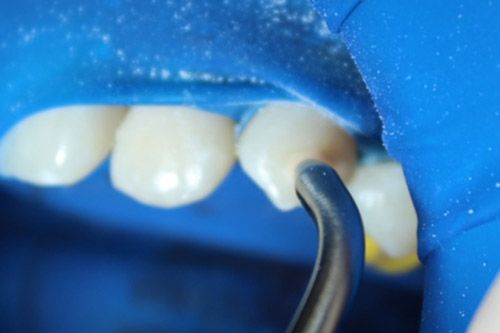

Se realizó aislamiento absoluto.

Se decidió utilizar un aeropulidor con bicarbonato Detarfar de Eufar por 1 minuto, con la finalidad de remover el tejido afectado.